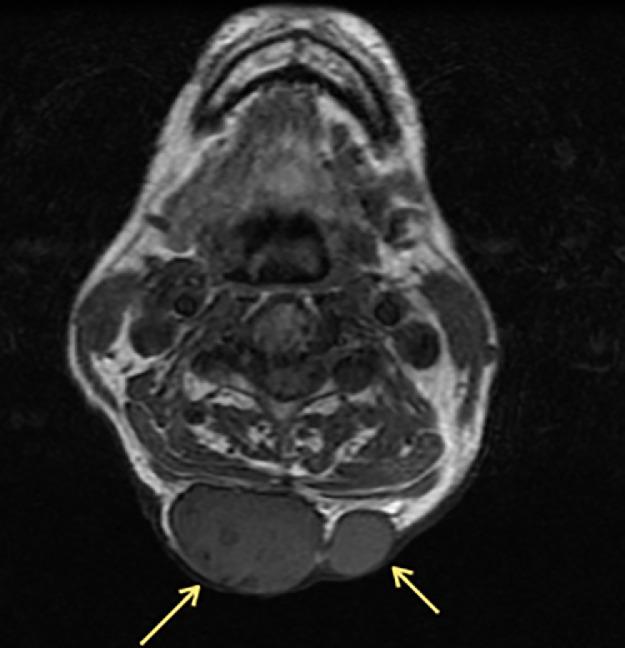

Malignant triton tumors are an extremely aggressive form of malignant peripheral nerve sheath tumor that display rhabdomyosarcomatous features. While these tumors are extremely rare, they have a much higher incidence in patients with neurofibromatosis-1. We present a case of a 64-year-old male with neurofibromatosis-1 who presented to the hospital with sudden worsening of shortness of breath and dysphagia to solids. Radiological examination revealed a large mass in the anterior mediastinum causing significant narrowing and displacement of the upper trachea and esophagus. Biopsy of the mass, done by interventional radiology, demonstrated features of an MTT. The mass was subsequently resected but without confirmation of tumor-free margins and the patient underwent adjuvant radiation therapy. Repeat radiological examination approximately four months later revealed growing malignancy and new metastases, which eventually contributed to the patient's death seven months after his presentation to the hospital.

恶性蝾螈瘤是一种极具侵袭性的恶性外周神经鞘瘤,具有横纹肌肉瘤特征。虽然这些肿瘤极为罕见,但在1型神经纤维瘤病患者中的发病率要高得多。我们报告一例64岁患有1型神经纤维瘤病的男性患者,他因突发呼吸急促和吞咽固体食物困难加重而入院。影像学检查显示前纵隔有一个大肿块,导致上气管和食管明显狭窄和移位。通过介入放射学对肿块进行活检,显示为恶性蝾螈瘤特征。随后切除了肿块,但未确认切缘无肿瘤,患者接受了辅助放疗。大约四个月后重复影像学检查发现肿瘤进展且出现新的转移灶,最终导致患者在入院七个月后死亡。